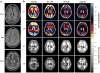

Rapid deformation of brain tissue in response to head impact or acceleration can lead to numerous pathological changes, both immediate and delayed. Modeling and simulation hold promise for illuminating the mechanisms of traumatic brain injury (TBI) and for developing preventive devices and strategies. However, mathematical models have predictive value only if they satisfy two conditions. First, they must capture the biomechanics of the brain as both a material and a structure, including the mechanics of brain tissue and its interactions with the skull. Second, they must be validated by direct comparison with experimental data. Emerging imaging technologies and recent imaging studies provide important data for these purposes. This review describes these techniques and data, with an emphasis on magnetic resonance imaging approaches. In combination, these imaging tools promise to extend our understanding of brain biomechanics and improve our ability to study TBI in silico.